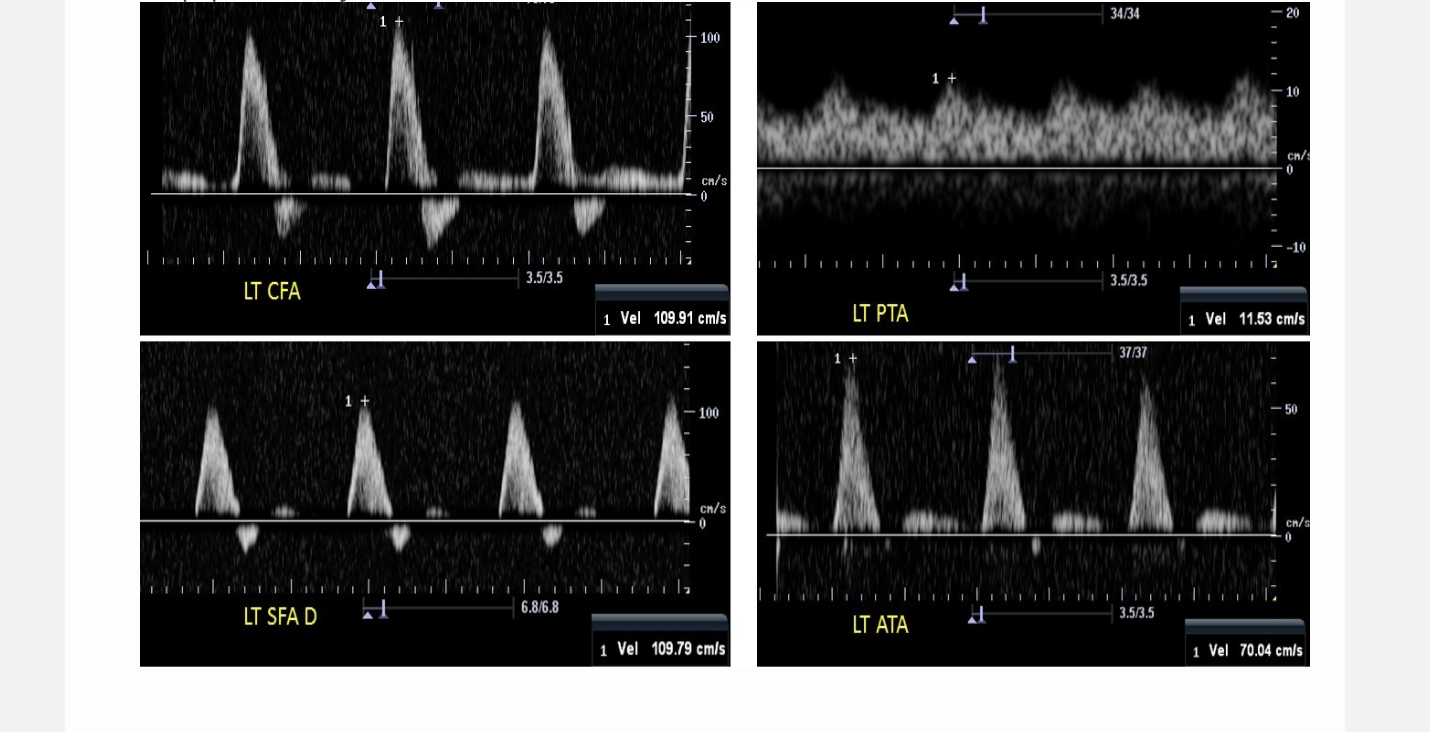

which measurements is used to differentiate inflow from outflow disease in the lower extremity arteries

.

a) acceleration time

b) S/D ratio

c) resistive index

d) pulsatility index

if the acceleration time is >140 m/s in both common femoral arteries, what disease is suspected

a) aortic disease

b) unilateral external iliac

c) bilateral internal iliac

d) normal flow

the distal femoral artery measures 2.75 m/s. what hemodynamic changes will be seen in the popliteal artery

a) increased acceleration time

b) high velocity, peaked waveform

c) increased diastolic flow reversal

d) decreased acceleration time

a 70% stenosis in the proximal femoral artery will cause the _____ in the mid femoral artery

a) acceleration time to increase

b) Reynold’s number to decrease

c) acceleration time to decrease

d) velocity to increase